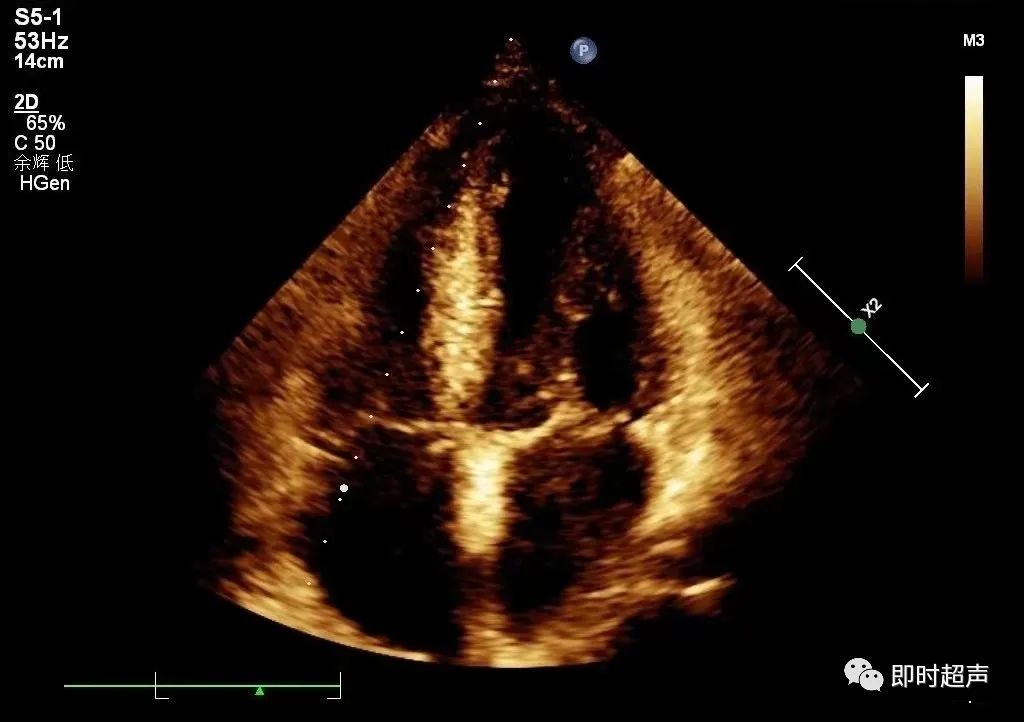

★右心房内径

测量切面:心尖四腔心切面;测量时相:收缩末期;右房长径:三尖瓣环平面中点到右房顶的距离;右房横径:房间隔中点到侧壁的距离,且垂直于右房长径。

★右心室的测量

测量时相:舒张末期;右室长径、中份及基底横径:心尖四腔心测量;右室前壁厚度及右室前后径:左室长轴切面测量;右室游离壁厚度:剑下切面三尖瓣腱索水平测量。